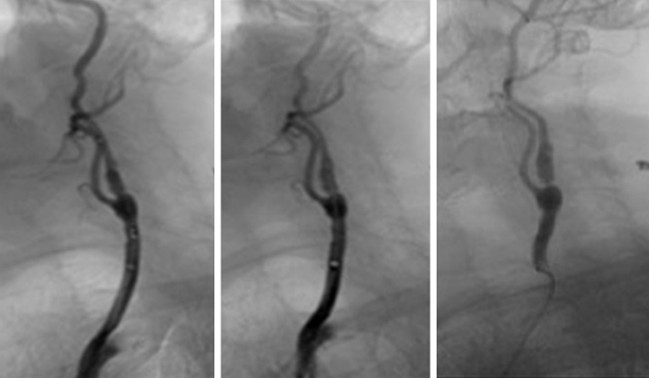

頸部解剖圖:說明頸源性頭暈與血管的關係

頸動脈

(3)頸椎內外血管扭曲:

抬頭、擺動頭頸部或長期姿勢不良等,導致頸椎內外血管流動不暢順,影響血液來往腦區域,導致頭暈、頭痛。

頸動脈血管 頸動脈受阻

Image source: Vascular Care Centre – “Carotid Arteries”

https://vascularcarecentre.com/for-patients/conditions/arterial-disease/carotid-arteries/